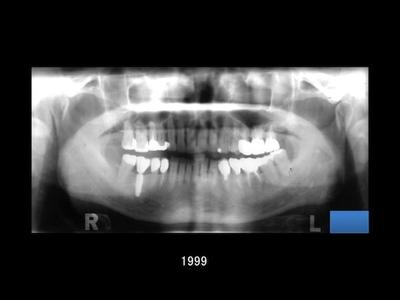

1995年に引き継いだ患者さんとの長いお付き合い

1995年上目黒歯科で勤務していた頃に、口腔外科専門医の先生から治療を引き継いだ患者さんがいらっしゃいました。 その当時、患者さんは重度の歯周病を患われており、まずは歯周基本治療と歯周外科治療を含む集中的な治療を、約1年かけて丁寧に進めました。

歯周状態が安定したのち、1997年に日本で認可されたばかりだった Ankylos Implant System を右の下顎に埋入。咬み合わせを回復させた後に、定期的な歯周病メインテナンスへ移行しました。

19年間の経過観察より

治療開始から現在まで、およそ19年が経過しました。 これまでの観察では、インプラント周囲の骨の状態も安定しており、セラミックの破折もなく、良好な状態を保っています。